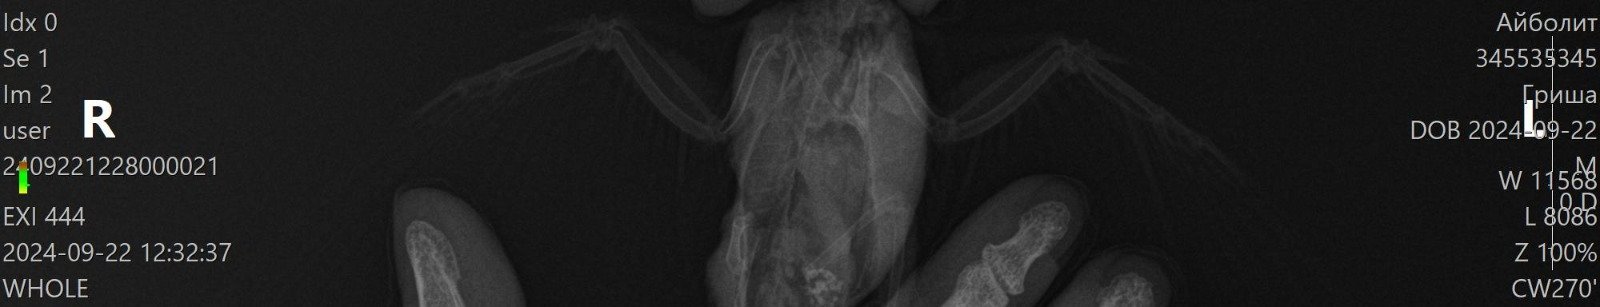

Вывих крыла и неоплазия

Помогите пожалуйста разобраться, птицу купили 2 недели назад, писала тут, что он не может летать, поняли это когда впервые попробовали выпустить. Сегодня дождались записи ветеринара, он посмотрел птицу, сделал снимок, сказал, что это вывих. Описание снимка сказали подождать, будет после того, как специалист из другого города опишет. В итоге вечером мне прислали описание снимка, прилагаю текст и теперь я совсем не понимаю. Там и травма и но образование. В ветеринарной клинике, где мы были молчат, больше никаких консультаций не дали мне. Можно ли что-то понять по приложенному сниму и описанию? Я верно понимаю, что дело не только в вывихе, а по снимку обнаружена какая-то опухоль?